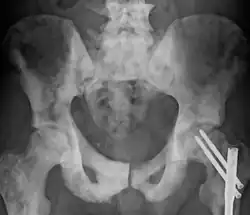

| Sclerosis of the bones of the pelvis due to prostate cancer metastases | |

Osteosclerosis is a disorder characterized by abnormal hardening of bone and an elevation in bone density. It may predominantly affect the medullary portion and/or cortex of bone. Plain radiographs are a valuable tool for detecting and classifying osteosclerotic disorders.[1][2] It can manifest in localized or generalized osteosclerosis. Localized osteosclerosis can be caused by Legg–Calvé–Perthes disease, sickle-cell disease and osteoarthritis among others. Osteosclerosis can be classified in accordance with the causative factor into acquired and hereditary.[2][1]